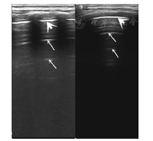

胸膜线(粗箭头)见正常肺脏胸膜线光滑、清晰、规则、宽度不超过0.5 mm和肺滑动征;A-线(细箭头)显示、等间距平行分布,多的可显示3条以上。

两组患儿LUS影像学表现见图1, 图2, 图3, 图4, 图5,检查结果见表1,其中CAP组中6例患儿动态观察,随病情恢复,6~19 d复查LUS可见肺实变范围逐渐缩小、支气管征减轻、胸膜线变清晰及A-线逐渐出现等(图1、图2);对照组仅见A-线,散在B-线(34.4%)(图5)。两组各项声像图特征比较差异均有统计学意义(均P<0.05)。